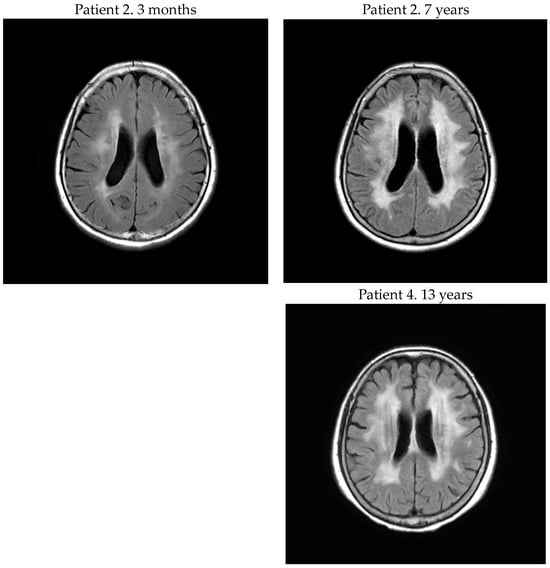

| 2 | F | 61 | 61 | 3 m | rapid | 2 | 2 | — | 2048 | 14,492.8 | 70 | no | 7 |

| 67 | 7 y | 3 | 3 | 3.89 | 1024 | 5083.7 | 43 | yes | 6 | ||||

| 4 | F | 65 | 78 | 13 y | rapid | 3 | 3 | 18.69 | 2048 | 7065.4 | 51 | yes | 5 |